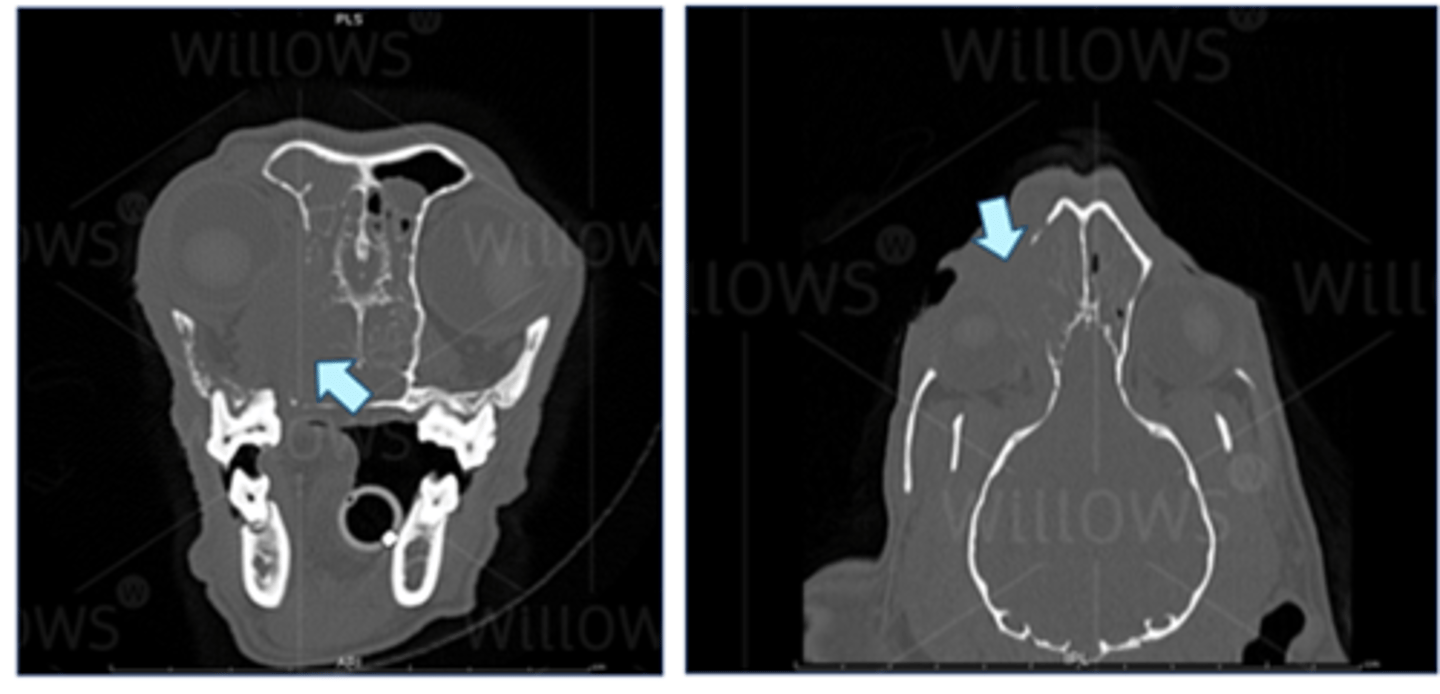

Cat with tear duct infection caused by foreign body (grass seed)

Labrador with swelling near tear duct